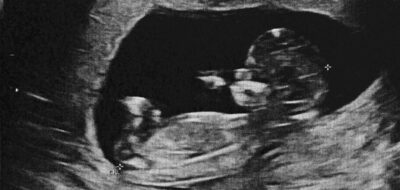

Pentru majoritatea oamenilor, alimente precum bananele sau cartofii sunt complet inofensive. Pentru Chloe Ramsey, însă, acestea au reprezentat ani la rând un pericol real, iar

MAI MULT